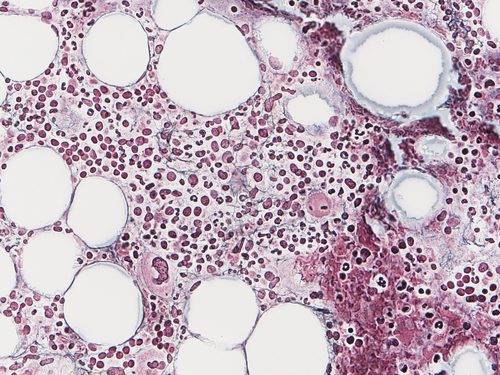

当科で経験できる多彩な症例と診療風景

当科では、日常診療から生まれるクリニカルクエスチョンを大切にし、臨床研究へとつなげています。特に力を入れているのが、深層学習(ディープラーニング)を用いた関節リウマチの診断支援システムの開発です。